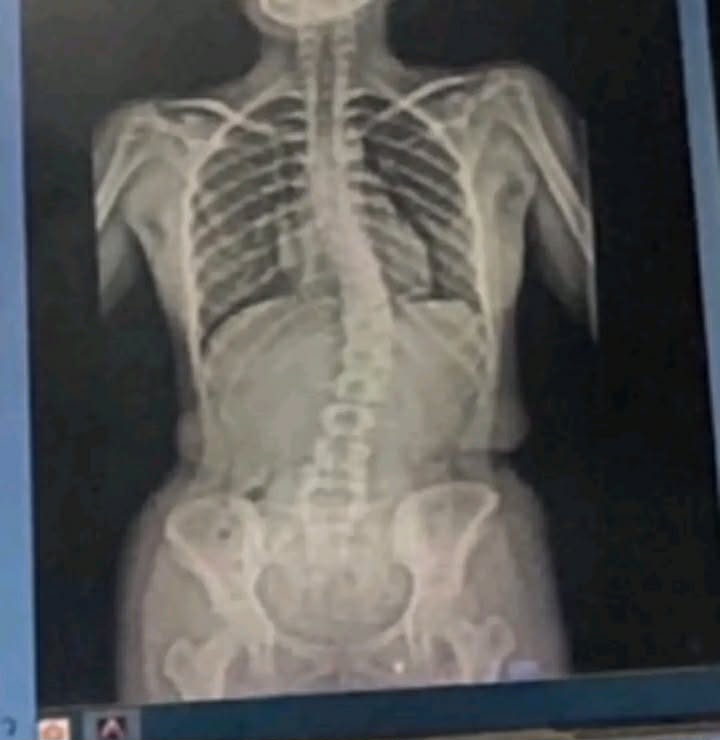

หลังจากที่เราเช็คแล้วรู้สึกว่าตัวเองเป็นแน่ๆจึงX-rayที่โรงพยาบาลโชคดีที่เราคดไม่ถึง20องศาถือว่าน้อยมากสามารถใส่เกราะหรือออกกำลังกายเพื่อพยุงไม่ให้สันหลังคดมากกว่าเดิมแต่ถ้าคดมากว่า45องศาหมอจะแนะนำให้ผ่าตัด

อันนี้เป็นตัวอย่างผลx-rayของเพื่อนเราที่คด20องศา